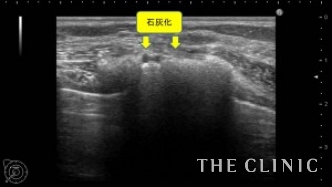

この方は、20年前に大胸筋下へバッグを挿入されています。今回、乳がん検診にてバッグの破損と被膜の石灰化を指摘され、バッグ抜去をご希望でご来院されました。エコーにて、両側のバッグ破損と被膜の石灰化を認めます。右側は脇の近くまでシリコンが漏れ出ている状態でした。

バッグ抜去後のエコー画像です。石灰化した被膜は、バッグを取り出すのが困難になり抜去したあとも石灰化が消えることはありません。